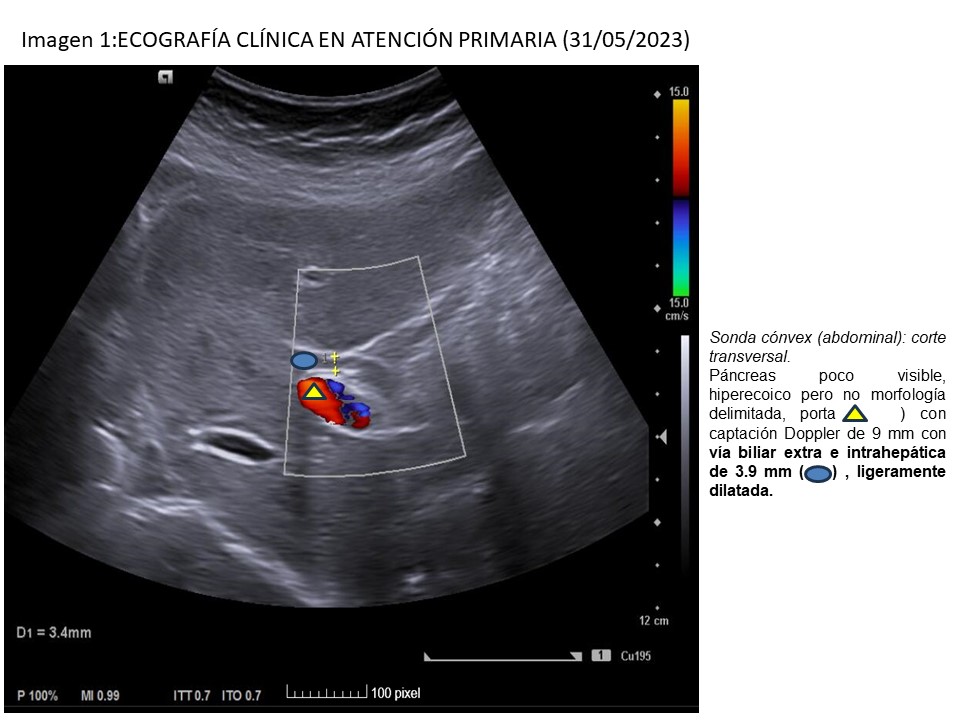

• Ecografía clínica-AP (31/05): páncreas poco visible, hiperecoico, no delimitado; porta de 9 mm con vía biliar ligeramente dilatada (3,9 mm), vesícula con barro biliar, paredes finas.

En este caso, el paciente padeció pancreatitis idiopáticas, debido a que el estudio etiológico no mostró alteraciones, incluso el TC previo fue normal. Sin embargo, en los episodios últimos se logró identificar la causa, siendo de origen biliar, gracias a la realización de una ecografía en el punto de atención (eco-POCUS), efectuada durante la consulta. Por tanto, la ecografía nos permite orientar el diagnóstico del episodio clínico en el momento de mayor sintomatología, situación que podemos evidenciar en Atención Primaria.